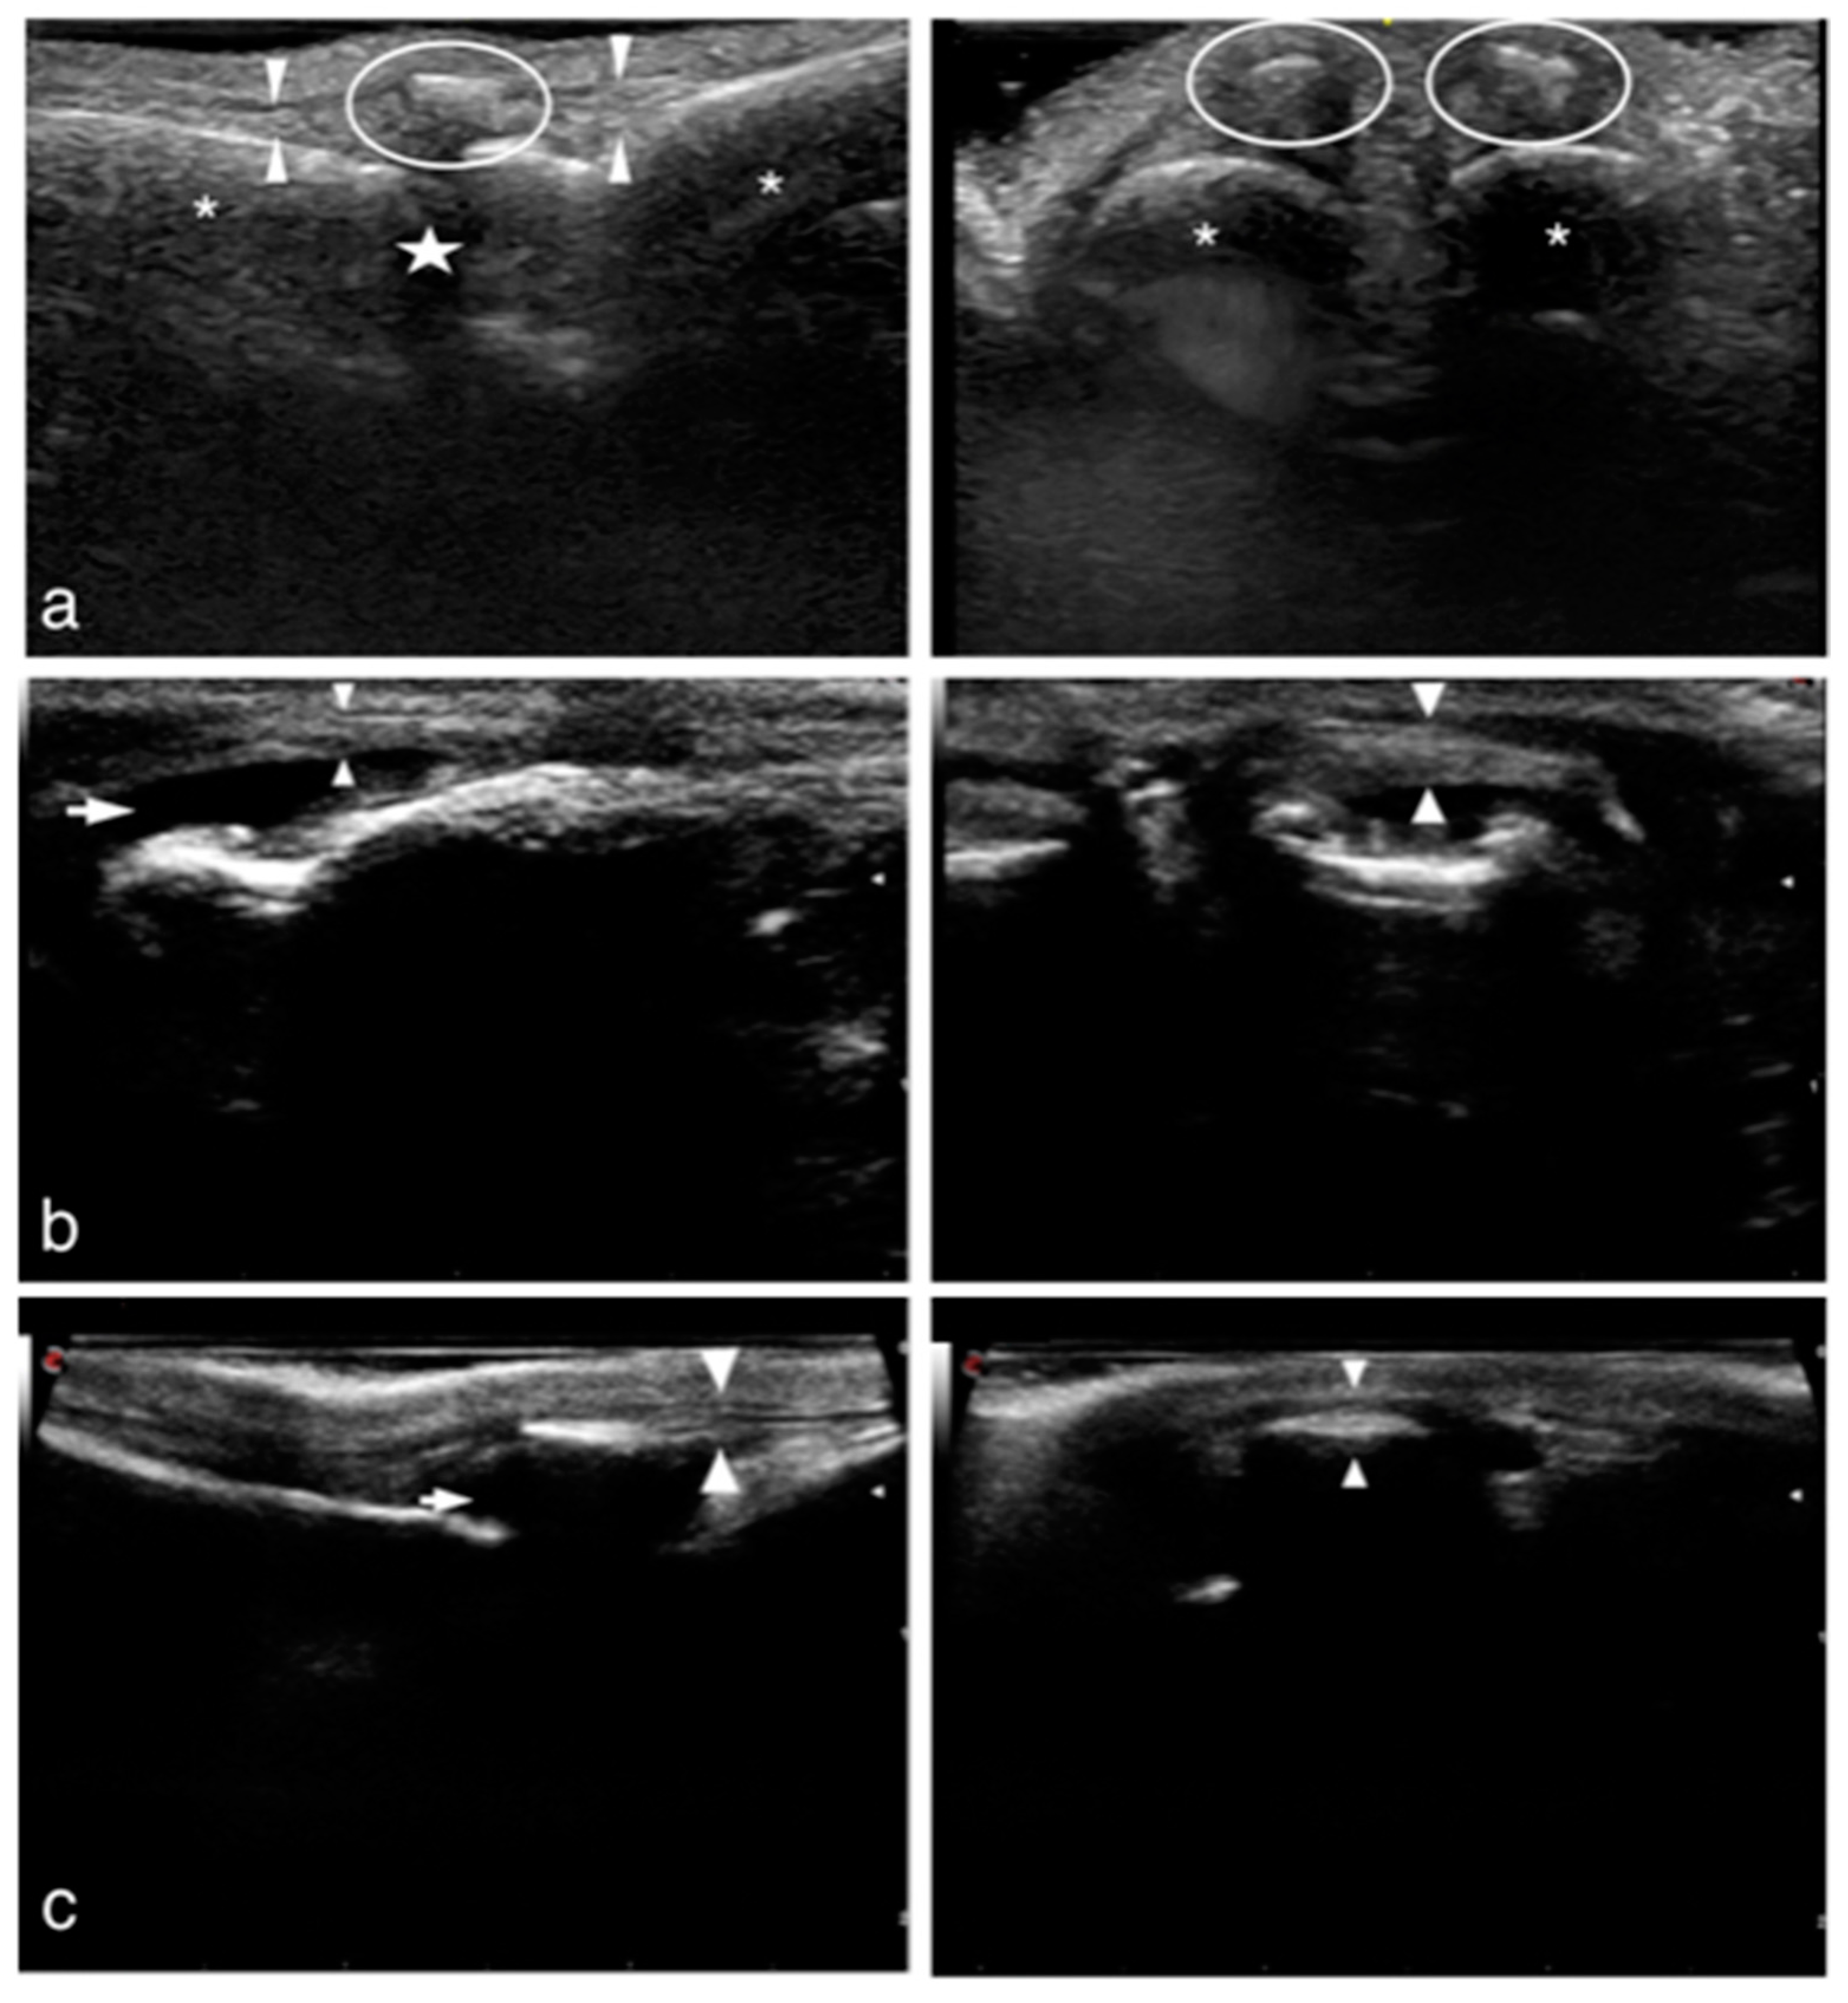

2.1.3. Ultrasonographic Examination (US)

2.2.3. Ultrasonographic Examination